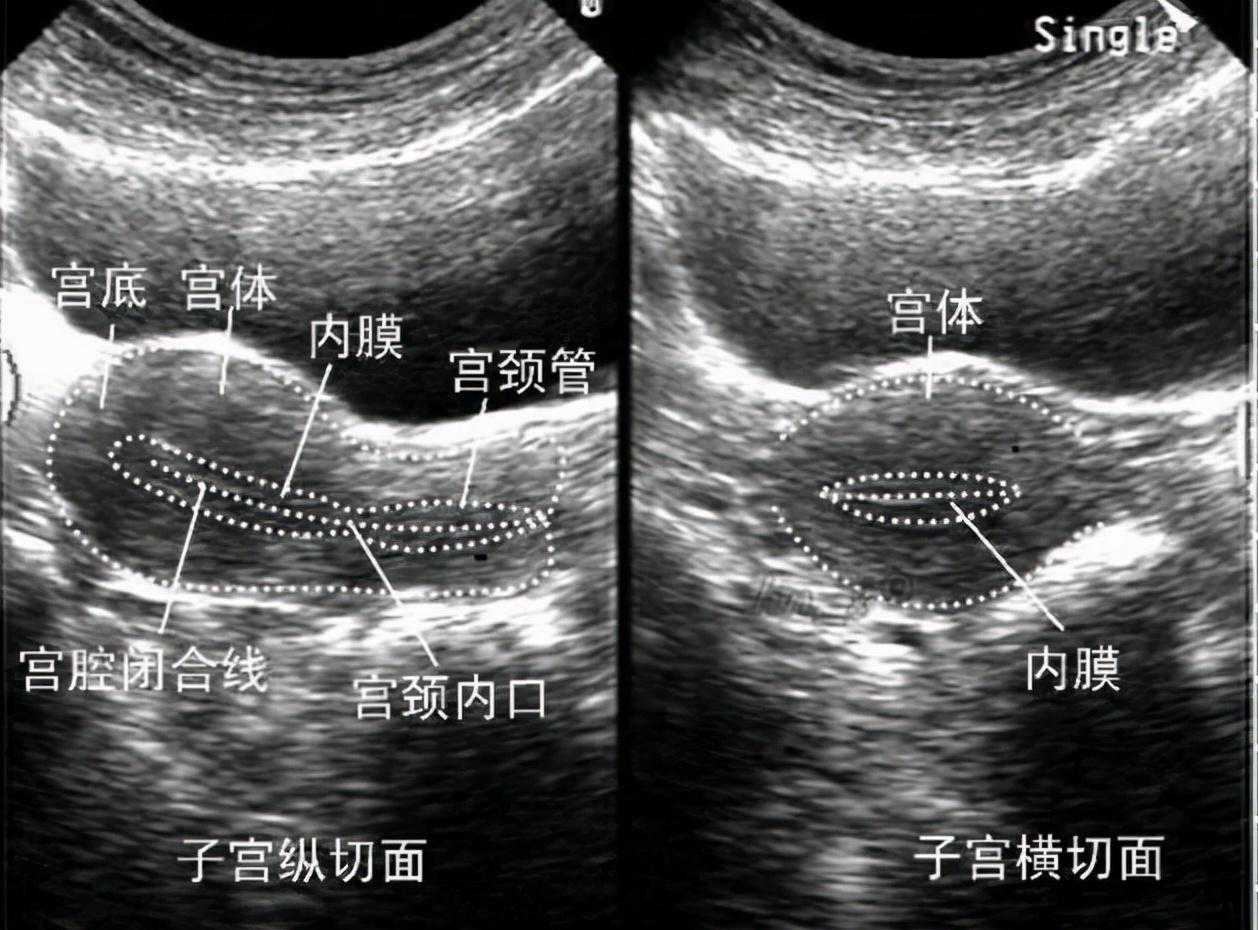

大家都知道,子宫内膜厚度在8mm到12mm是最适宜受精卵着床的。一般来说,子宫内膜厚度小于7mm,就会诊断为子宫内膜薄。如果试管移植周期,患者子宫内膜7mm,建议取消周期。有研究表明,如果子宫内膜厚度小于6mm,怀孕成功率显著下降。